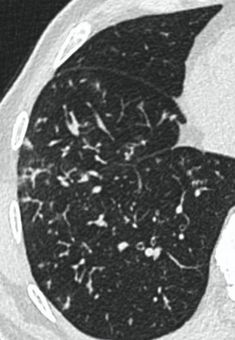

Методы лучевой диагностики применяют для выявления COVID-19 пневмоний, их осложнений, дифференциальной диагностики с другими заболеваниями легких, а также для определения степени выраженности и динамики изменений, оценки эффективности проводимой терапии.

КТ имеет высокую чувствительность в выявлении изменений в легких, характерных для COVID-19. Применение КТ целесообразно для первичной оценки состояния ОГК у пациентов с тяжелыми прогрессирующими формами заболевания, а также для дифференциальной диагностики выявленных изменений и оценки динамики процесса. КТ позволяет выявить характерные изменения в легких у пациентов с COVID-19 еще до появления положительных лабораторных тестов на инфекцию с помощью МАНК. В то же время, КТ выявляет изменения легких у значительного числа пациентов с бессимптомной и легкой формами заболевания, которым не требуется госпитализация. Результаты КТ в этих случаях не влияют на тактику лечения и прогноз заболевания при наличии лабораторного подтверждения COVID-19. Поэтому массовое применение КТ для скрининга асимптомных и легких форм болезни не рекомендуется.

3. Применение лучевых методов у пациентов с симптомами ОРВИ легкой степени тяжести и стабильном состоянии пациента, возможно только по конкретным клиническим показаниям, в том числе при наличии факторов риска, при условии достаточных технических и организационных возможностей. Методом выбора в этом случае является КТ легких по стандартному протоколу без внутривенного контрастирования или РГ при ограниченной доступности КТ. Использование УЗИ в этих случаях нецелесообразно. Применение КТ исследования в сроки ранее 3 - 5 дней с момента появления симптомов заболевания является нецелесообразным.

4. Все выявляемые при лучевых исследованиях признаки, включая КТ-симптомы, не являются специфичными для какого-либо вида инфекции и не позволяют установить этиологический диагноз. Вне клинической (эпидемической) ситуации они не позволяют отнести выявленные изменения к пневмонии COVID-19 и дифференцировать их с другими пневмониями и невоспалительными заболеваниями. Данные лучевого исследования не заменяют результаты обследования на РНК SARS-CoV-2. Отсутствие изменений при КТ не исключают наличие COVID-19 и возможность развития пневмонии после проведения исследования.

15. Рекомендации по формированию описаний и оценке изменений в легких и ОГК при имеющейся/подозреваемой пневмонии COVID-19 представлены в Приложении 1.